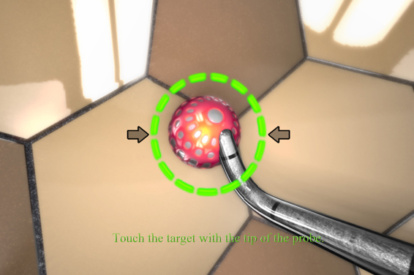

ARTHRO Mentor is an effective tool for arthroscopic surgery skills acquisition. With over 15 years of validation studies, it offers a line of simulated procedures, covering the 3 major joints (shoulder, knee, and hip) combining physical anatomical models with 3D images and dynamic haptic sensation, to allow users to learn key aspects of the procedures while providing tissue sensation.

- Reduces training time and improves the learning curve

- Adaptive tactile sensation on drilling, suturing, and shaving

- A library of modules with 80+ tasks, cases, and didactics